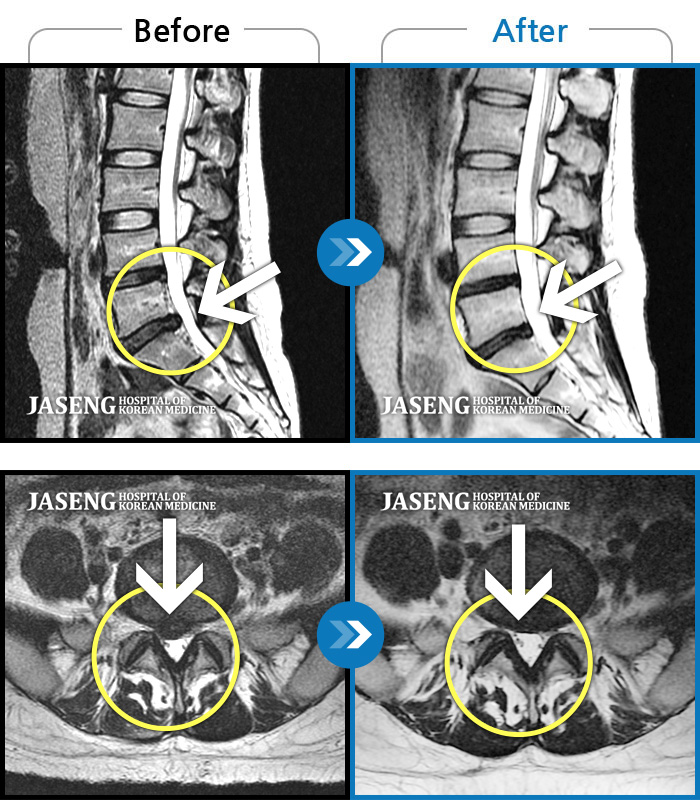

허리디스크

안산 · 조창현 원장

허리 통증 및 오른쪽 다리로 내려가는 심한 통증으로 혼자 보행 어려워 응급 내원

촬영시기

2019.09.21 ~ 2021.10.05

2021.10.08

조회수 2,669